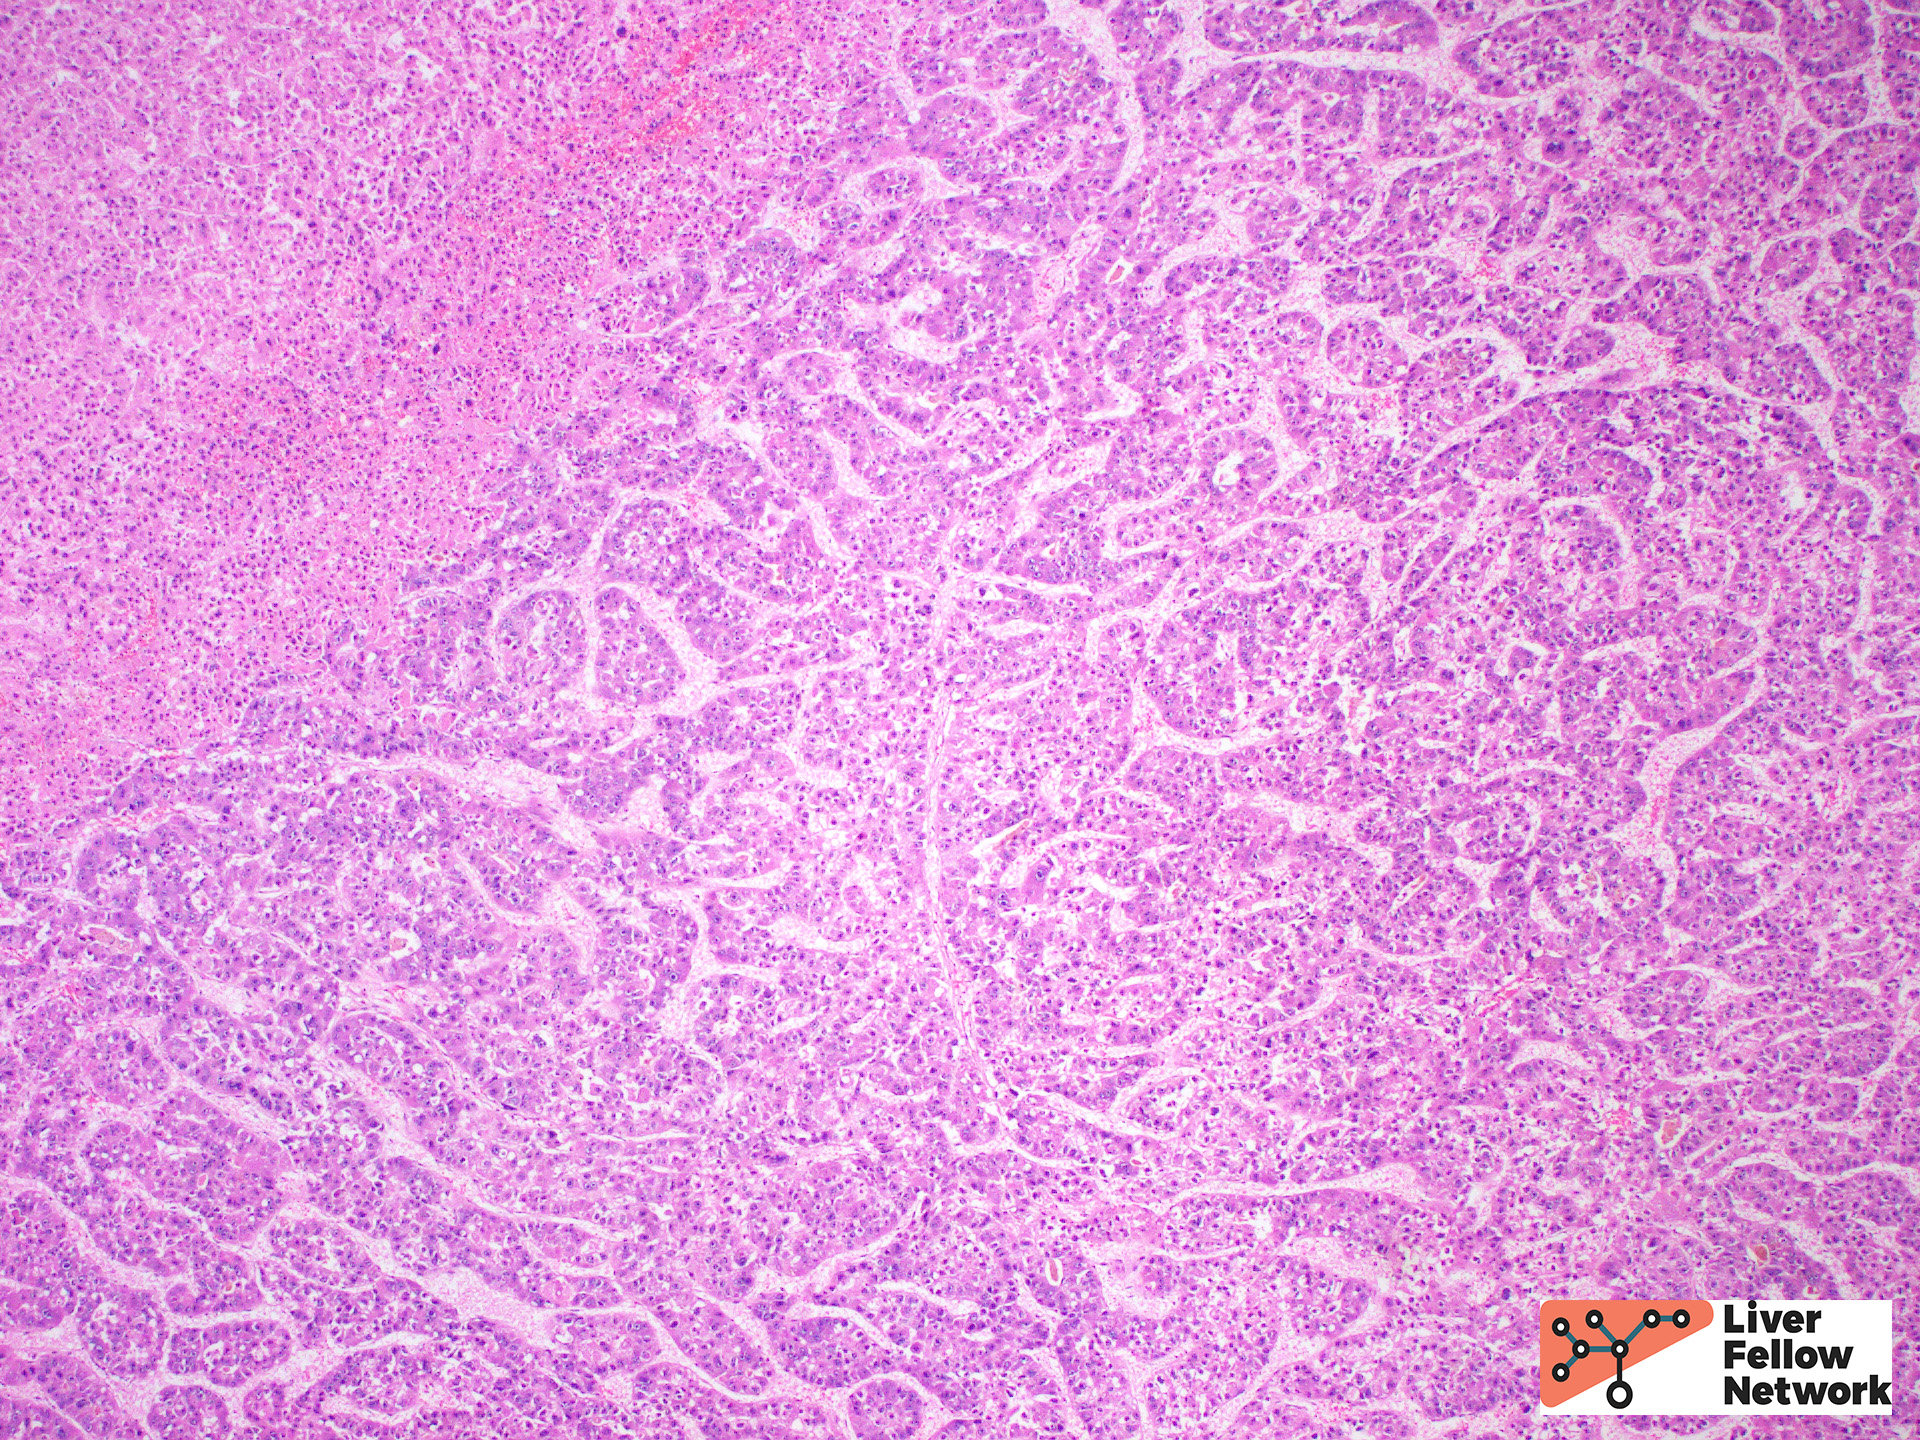

The most common architectural patterns are solid, trabecular (in which tumor cells grow in thickened hepatic plates separated by sinusoidal spaces), and acinar/pseudoglandular patterns (in which the tumor cells form small nests with central degeneration that resembles glands), Figure 7. However, the poorly differentiated HCCs will often grow as solid masses and will not resemble normal hepatocytes (Figure 8).